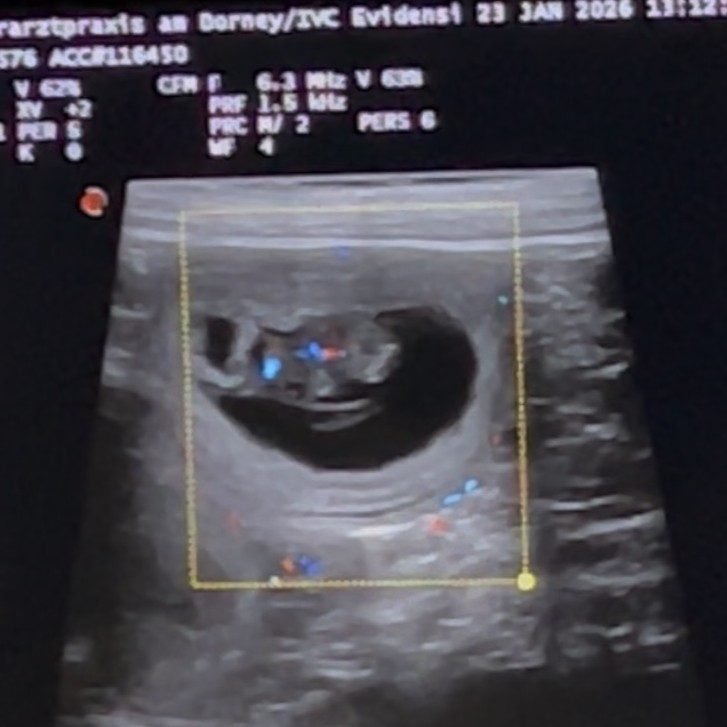

Emmy trägt Leben in sich –

wir erwarten Welpen

Mit großer Freude dürfen wir bekanntgeben, dass Emmy tragend ist. Am 23. Januar 2026 wurde die Trächtigkeit durch Frau Dr. Möhrke bestätigt. Im Fachjargon spricht man von vitalen Anlagen, ein schöner Moment, der uns sehr glücklich macht.

Emmy geht es hervorragend, sie ist entspannt, fröhlich und genießt die besondere Aufmerksamkeit, die ihr nun zusteht. Für uns beginnt jetzt eine spannende und intensive Zeit, in der wir Emmy liebevoll begleiten und uns auf die kommenden Wochen vorbereiten.